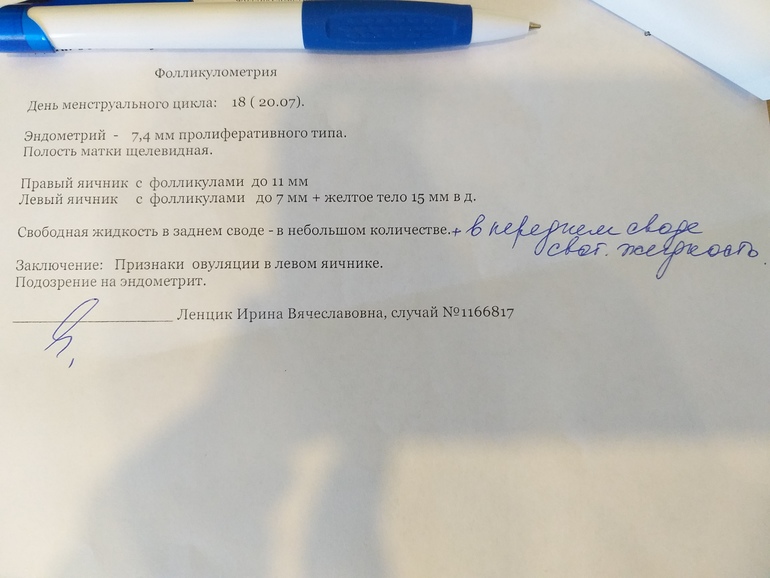

Сходила сегодня на узи фолликулометрию, таких результатов не ожидала((

По словам врача много свободной жидкости и она везде, плюс какое-то расширение (какое и чего непонятно, в заключении про это ничего не сказано), врач говорит что это указывает на воспаление, эндометрит.

Плюс я так понимаю эндометрий очень тонкий для 18 ДЦ.

Посмотрите пожалуйста заключение, может у кого так было? Что в итоге оказалось? Наступала ли беременность при такой толщине эндометрия??